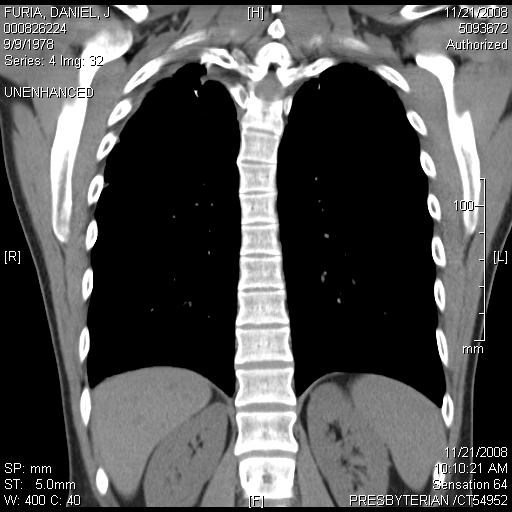

Lung Blebs

"Blebs" are weak spots that form at the top of the lung. These weak spots can leak air and cause a lung to collapse. This image shows dozens of small blebs on each of my lungs. This cat scan image was taken from above, looking down on to the top of the lung. (In other words try to imagine that you are floating up above me, looking down at the top of my head. If you could see layer by layer into my body, like the CT scan, you would then eventually see the tops of my lungs). The big dark black circle in the middle of the image is my windpipe.